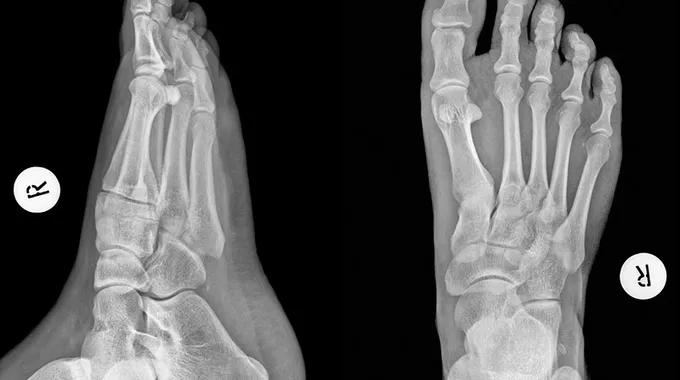

تشوه إبهام القدم: الأسباب والعلاج

يؤكد الدكتور زوهيروف أن الاعتقاد السائد بأن الورم المفصلي في القدم، وبالأخص في منطقة إبهام القدم، هو حالة سطحية أو تجميلية بحتة هو تصور خاطئ. فظهور هذا النتوء يرتبط بعدة عوامل عضوية، من بينها الاستعداد الوراثي، إلى جانب تسطح القدم وضعف الأربطة، مما يؤدي إلى تغيير تدريجي في شكل مقدمة القدم. كما يشير إلى أن هذه العوامل تتفاعل مع بعضها البعض لتؤدي إلى تفاقم الحالة.

تشير الإحصائيات إلى أن النساء هن الأكثر عرضة للإصابة بتشوه إبهام القدم، وذلك بسبب ارتداء الأحذية ذات الكعب العالي (أكثر من 4 سم) أو الضيقة من الأمام. فهذه الأنواع من الأحذية تؤثر على الميكانيكا الحيوية للمشي وتوزيع الوزن، مما يؤدي مع مرور الوقت إلى انحراف الإبهام نحو الأصابع الأخرى وظهور الورم بشكل واضح.

يضيف الخبير أن الورم لا يؤثر فقط على المظهر الجمالي للقدم، بل يسبب أيضًا ألماً مزمناً وصعوبة في المشي. مما يجعل العثور على حذاء مريح أمراً معقداً. وقد يعتقد بعض الأشخاص أن العلاج الذاتي أو الاعتماد على الأحذية التقويمية قد يكون كافياً، لكن هذه المحاولات غالبًا ما تؤخر تفاقم المشكلة فقط.

مع تطور الحالة، يزداد الألم ويحدث العرج، مما يجعل الخيار الوحيد المتبقي هو الخضوع للتدخل الجراحي كوسيلة فعالة لعلاج المشكلة. لذا، من الضروري إجراء الفحوصات اللازمة واستشارة المختصين لتحديد أفضل سبل العلاج.